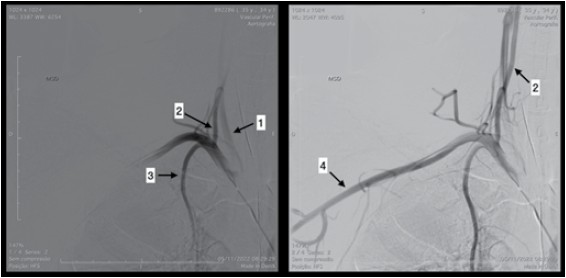

Observe a figura.

(Arquivo pessoal: imagem usada com autorização)

Com base na anatomia angiográfica apresentada na figura, assinale a alternativa correta.